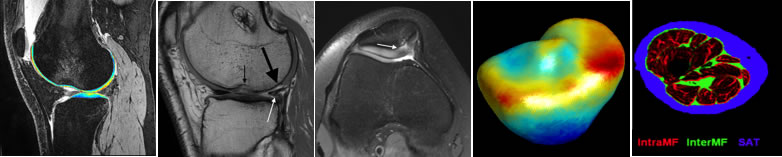

MR T1ρ and T2 relaxation times have shown to be promising imaging biomarkers for early cartilage degeneration, and prediction of disease progression. However, many challenges to clinically applying these techniques remain, including lack of standardized acquisition and quantification methods, and long acquisition time. We have implemented MAPSS T1ρ and T2 imaging sequences on three major MR platforms (Siemens, GE and Philips) and have performed multisite multivendor cross validation and reproducibility evaluation, sponsored by the Arthritis Foundation. The next step is to develop fast T1ρ and T2 imaging techniques using novel MRI reconstruction and evaluate the reproducibility and clinical significance of the technique in a multivendor multicenter setting in volunteers and patients with osteoarthritis. A dedicated MSK calibration phantom will be also developed.

Anterior Cruciate Ligament (ACL) injury is a proven high-risk factor for post-traumatic osteoarthritis (PTOA) development despite ACL reconstruction (ACLR). However, our understanding of PTOA development after ACLR is limited, and reliable biomarkers that provide early diagnosis and prognosis are still lacking. In this study, we will collect quantitative MRI data in the Multicenter Orthopaedic Outcomes Network (MOON) nested cohort at 10 years after ACLR to characterize for the first time long-term structural damage and articular cartilage degeneration after ACLR, understand their patterns and relationship to patient outcomes, and identify modifiable predictors for PTOA at 10 years after ACLR from pre-operative and early postoperative time points. Furthermore, the MRI measures, such as cartilage T1r and T2, at 10 years will also serve as potential predictors for future PTOA development (for those who do not develop PTOA at 10 years), failure of the ACLR graft or contralateral ACL, and additional arthroscopic surgery at the 20 years post-ACLR.

Lateral patellar instability is a traumatic event that consistently leads to cartilage damage.  Approximately 50% of patients treated for patellar instability develop patellofemoral osteoarthritis (OA) within 25 years, with a higher risk of OA for patients with recurrent instability.  The investigators have initiated this line of research to improve understanding of post-traumatic OA related to patellar instability, identify patients at greatest risk of post-traumatic OA, and optimize treatment methods to reduce the risk of OA. Quantitative MRI, statistical shape modeling and computational models will be used to provide a comprehensive evaluation of the joint structure, tissue composition and functions.

Arthroscopic partial meniscectomy (APM) is the most commonly performed ambulatory orthopaedic procedure in the United States, with almost half of these procedures performed in patients over 45 years of age, often with concomitant osteoarthritis.  At present, there is no preoperative tool that is available which can predict the likelihood of having a successful outcome after APM in this patient population.  The objective of this study is to identify the preoperative MRI predictors in patients 45 years old and older who will have no clinically meaningful improvement in PROMs after APM. The tools developed from this study will be useful to reduce unnecessary surgeries and cost to the healthcare system which we plan to test in a future randomized control trial.